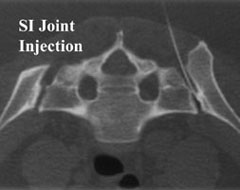

The actual injection only takes a few minutes and consists of a mixture of local anesthetic and steroids. The injection itself does not hurt. Doctors use fluoroscopy to insure the needle is correctly placed before medicine is injected. The patient can usually return to normal activity the following day. There is an immediate effect from the local anesthetic which wears off over a few hours. The cortisone starts to work in about 3 to 7 days and it can last up to a few months. Several injections may be necessary over a period of a few weeks to 6 months.